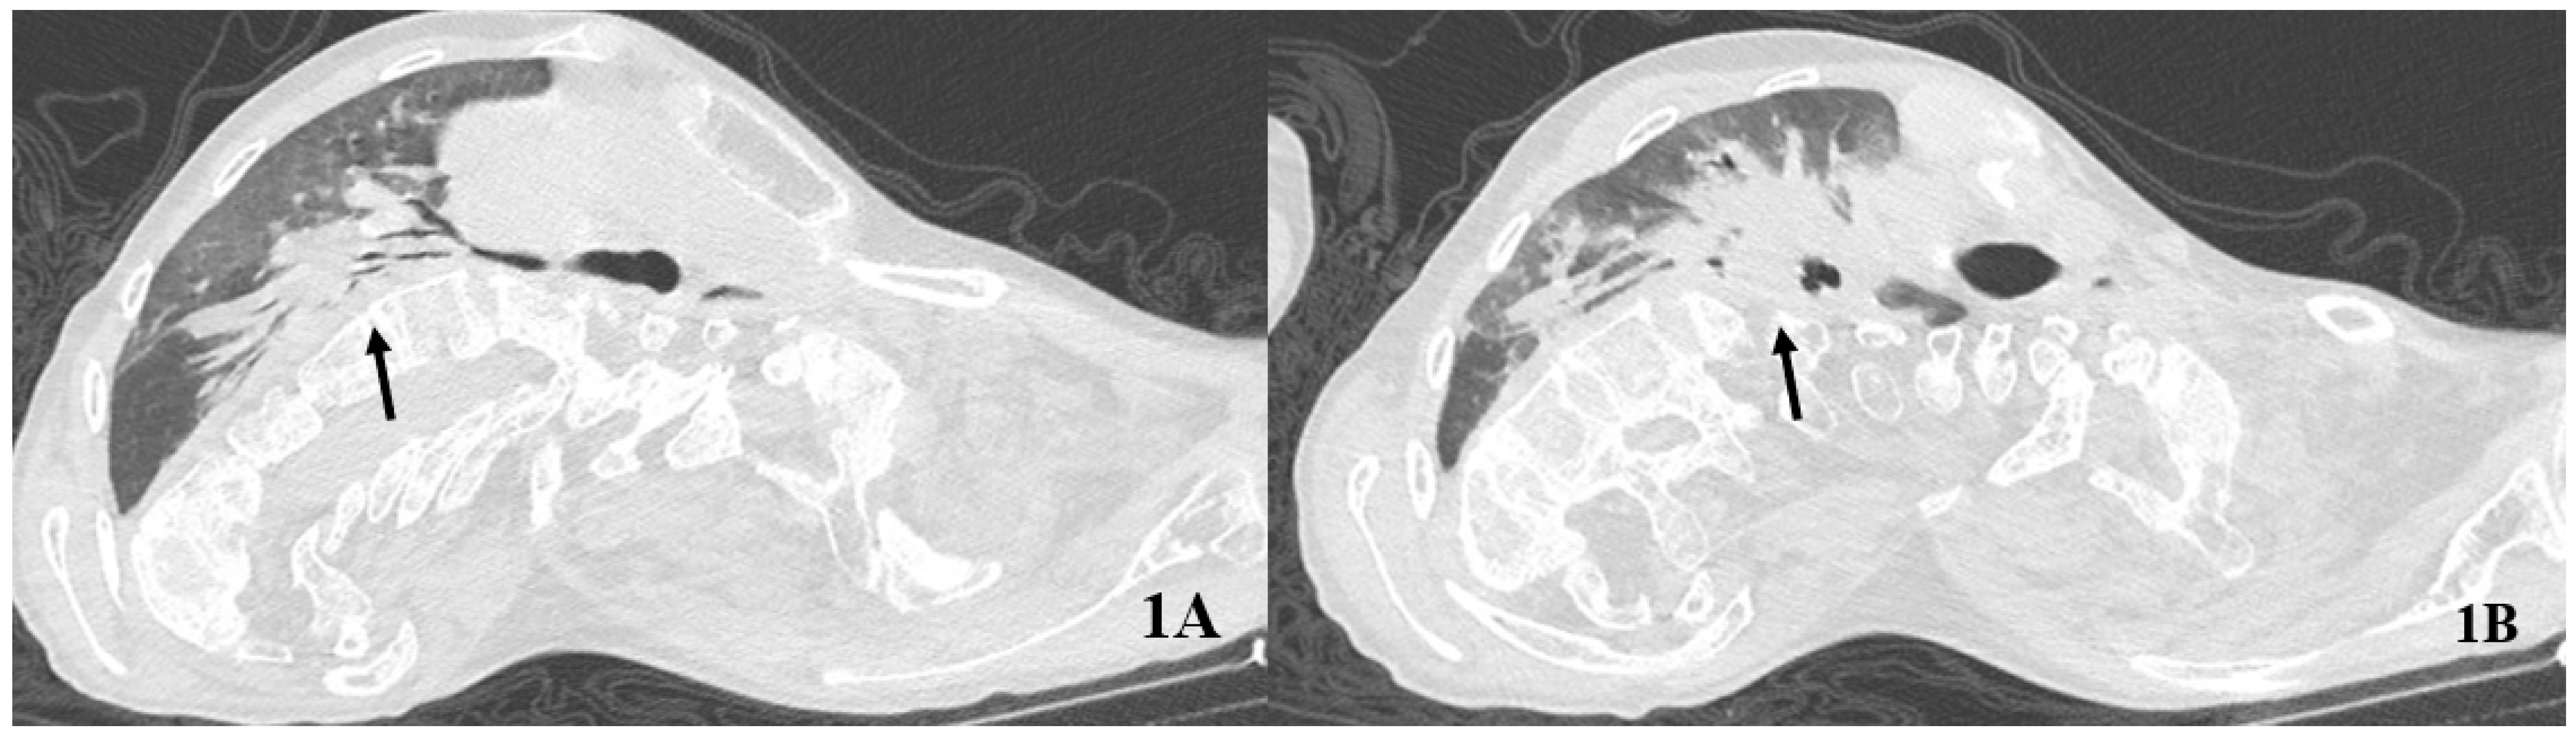

COVID-19 caused fever, respiratory difficulties, and seizures at the onset. The subject was unvaccinated for SARS-CoV-2. He accessed the emergency room and underwent blood gas analysis showing a partially compensated hypercapnic respiratory failure (pH 7.38, pCO2 79 mmHg, pO2 56 mmHg, lactate 0.8 mmol/L, HCO3− 38.3 mmol/L). The high-resolution computed tomography (HRCT) of the chest showed ground-glass opacities and consolidations bilaterally (Figure 1). Atelectasis of the right lower lobe was also described.

Figure 1.

Baseline computed tomography of the chest. The arrows indicate an extensive consolidation from the right hilum (A) to the right lower lobe (B).